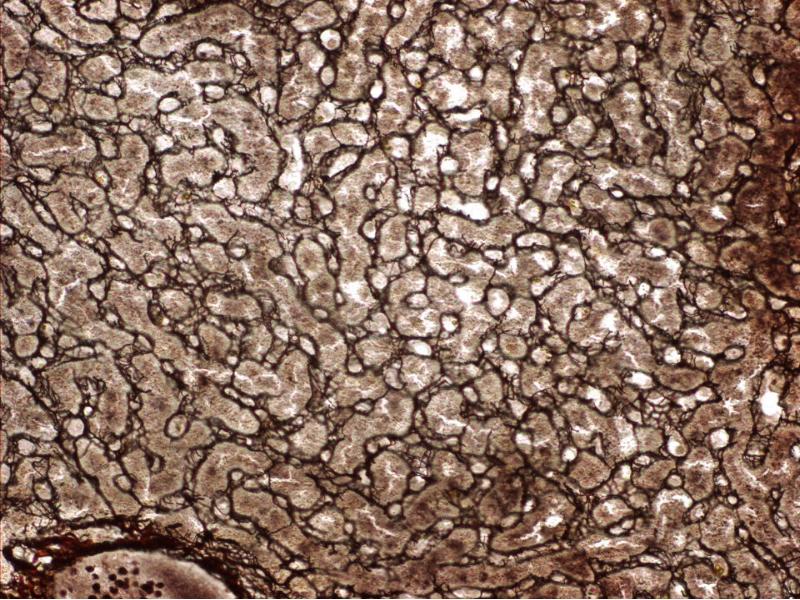

| Spleen |

| Red pulp |

White pulp |

Connective tissue

Sinusoids

Blood

|

Lymphocytes |